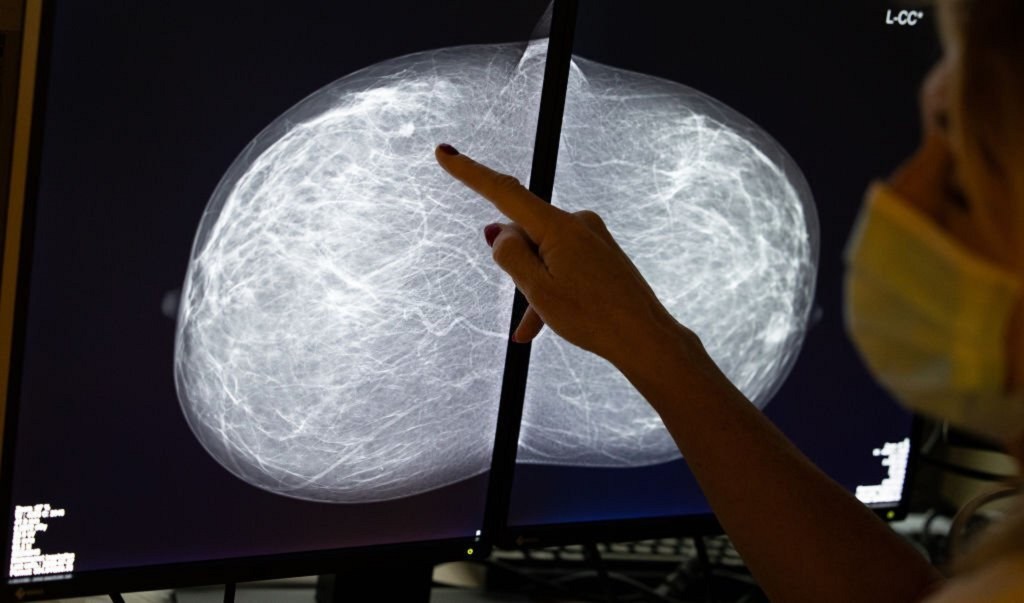

乳房X光造影檢查主要用於40歲以上女性的早期病變篩查。定期檢查有效及早發現乳房病變,提高治療機會及存活率。

乳房X光造影是一種重要的乳癌篩查工具,X光造影儀器會分別上下和左右按壓每邊乳房,兩邊乳房先後拍攝,過程中女士可能會感到數秒的不適,放射師確認 X 光片能清楚呈現乳房組織後,拍攝便完成。

由於會把胸部上下夾著再照 X 光,亦被稱為「夾胸檢查」,隨著科技發展出現2D及3D的乳房X光造影檢查。

乳房X光造影能有效在患者沒摸到腫塊前判斷腫塊是否癌症,特別是極小,邊緣不清,形狀不規則的腫塊及鈣化等不尋常情況。

乳房X光造影檢查在醫學界廣泛使用超過50年,輻射量極低,發生癌症的風險微乎其微,可檢測極小的鈣化腫瘤,對早期病變的偵測率高於超聲波,尤其對原位癌的偵測性佳。